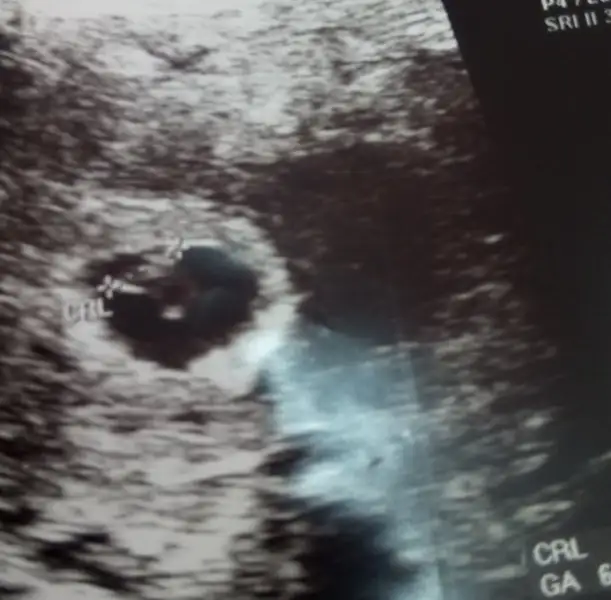

Merhabaa biz de 7+6 yken böyleyiz teoriye göre tahmin yapar mısınız?karından usg

Eklentiler

• IMG_5570.webp

7,2 KB · Görüntüleme: 231